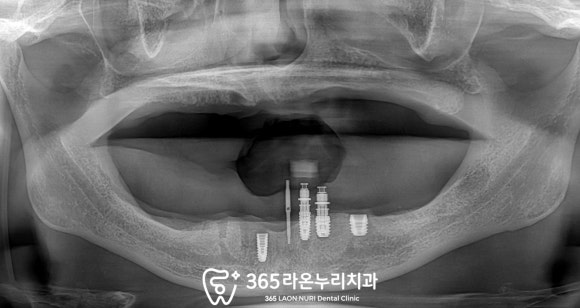

환자의 동의하에 남은 치아를 모두 뽑았으며

하악의 초기 고정력을 잘 받을 수 있는 곳에

최소한의 개수만 식립하기 위해

위치를 확인하고 있는 모습입니다.

픽스처의 식립 위치와 깊이는

아래턱뼈 내에 있는 해부학적 구조에

영향을 끼치지 않게

신중하게 심어드렸습니다.